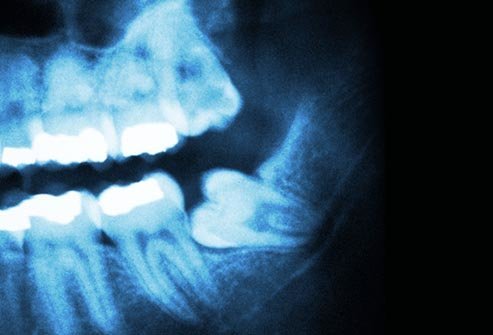

Dhëmbët e Ndikuar

Një dhëmb tek të rriturit që nuk del ashtu siç duhet është i “ndikuar”. Kjo zakonisht ndodh kur një dhëmb është mbërthyer kundër një dhëmbi tjetër, kockave, apo indeve të buta. Nëse nuk ju pengon dentisti mund të ju rekomandojë ta lini atë. Por në qoftë se ju dhemb apo ju shkakton probleme, një kirurg duhet të u’a largojë atë.